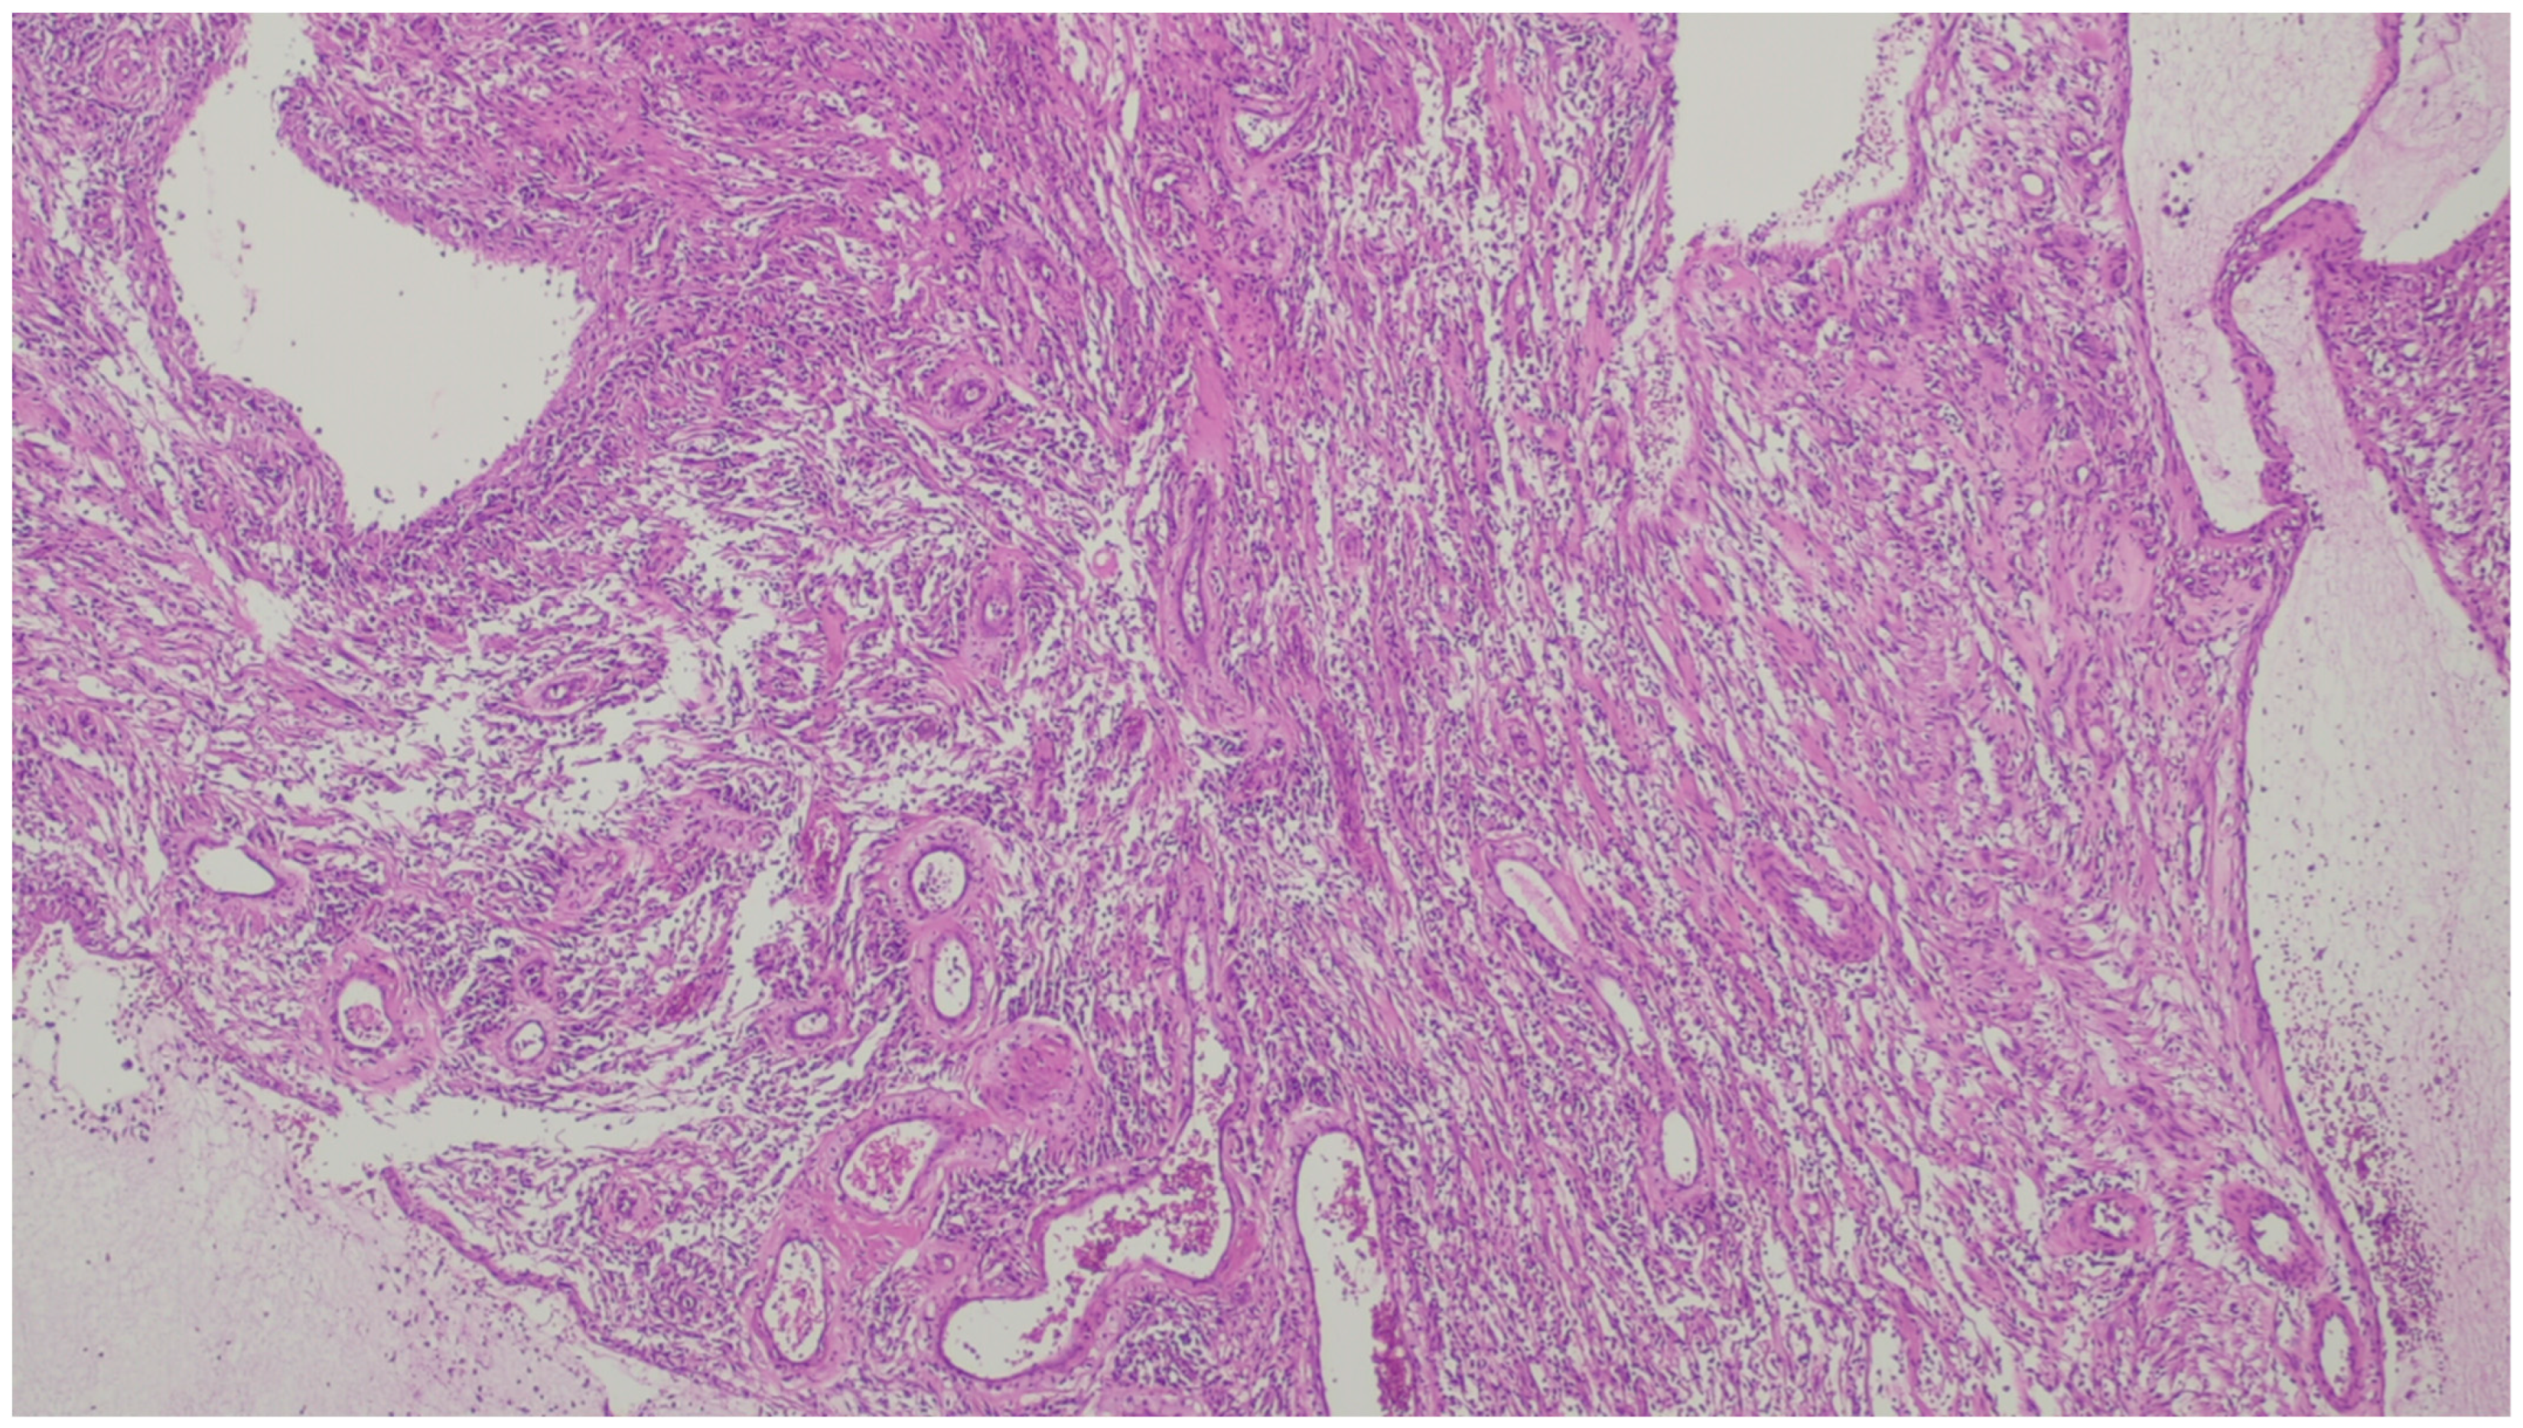

| Synovial sarcoma | Middle-aged to older adults | Stomach | Polypoid or an ulcerated lesion | Monophasic with uniform spindle cells with scarce matrix or biphasic with glandular elements | SS18/SSX positivity. Focal positivity for keratins and EMA in monophasic lesions and strong staining in the biphasic version |